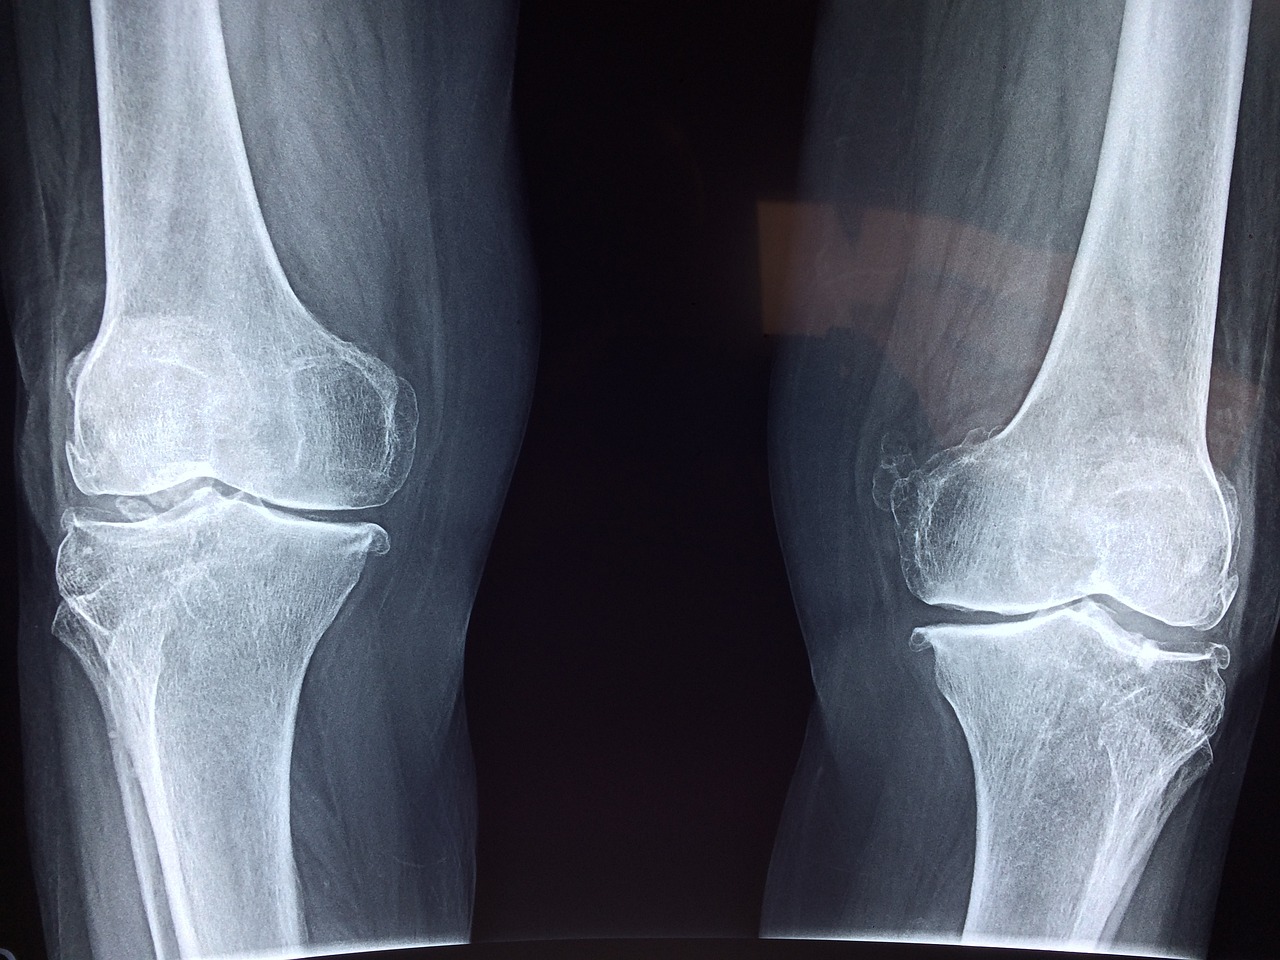

골다공증 검사는 뼈의 밀도와 강도를 평가하여 골절 위험을 판단하는 데 사용됩니다. 주요 검사 방법은 골밀도 검사로, DXA(이중 에너지 X선 흡수계측법)가 가장 널리 쓰입니다.

DXA는 척추와 대퇴골의 뼈 밀도를 측정하여 골다공증 여부를 판단합니다.

- 주요 측정 부위: 척추, 대퇴골, 손목 등이 일반적입니다.